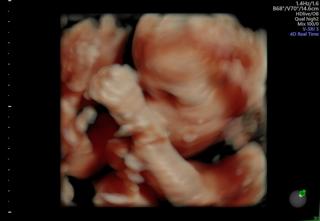

男の子です!写真では手で顔を隠しててわからないけど、動画だと私似かな!?と(*^^*)800gくらいになったみたいで、どんどん大きくなってて嬉しいです♪